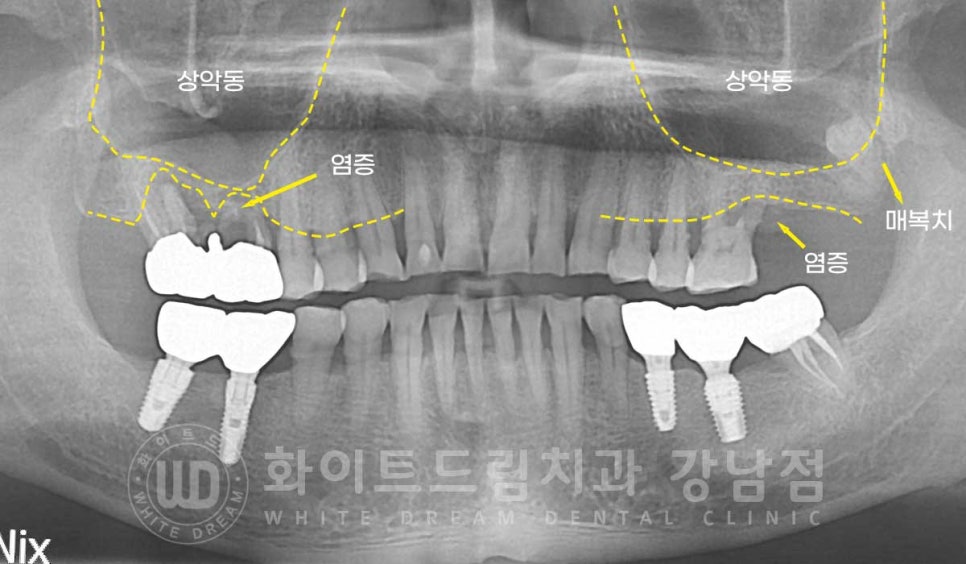

환자분의 초진 X-RAY 사진입니다.

환자분의 X-RAY 사진을 보니 환자분이 불편함을 호소하시는

16, 17번 크라운 주위로 염증이 크게 자리 잡고 있는 것이 확인됩니다.

신경치료를 한 치아이기 때문에 큰 통증은 없지만 심하게 흔들리고 악취가 나는 것 같다고

이야기를 하셨는데요.

아마 노화 & 치주 질환으로 잇몸 염증이 발생하여 잇몸이 점점 내려앉았고

보철과 잇몸 사이 틈으로 이물질이 저류하면서 크라운 주위 염증이 크게 자리 잡게

된 것으로 추측되었습니다.